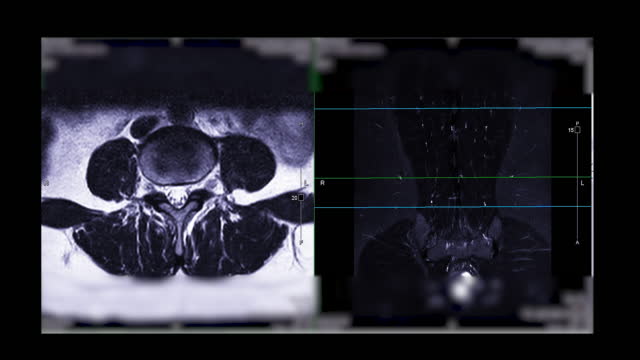

척추관협착증은 척추 주변의 근육과 인대가 퇴행하여 척추관 내 황색 인대가 비정상적으로 부풀어 오르면서 발생하는 퇴행성 척추질환 중 하나입니다. 이 질환은 가까운 거리도 통증으로 인해 걷기가 어려워지는 특징을 가지고 있으며, 새벽에 다리에 통증을 느끼는 경우가 많습니다.